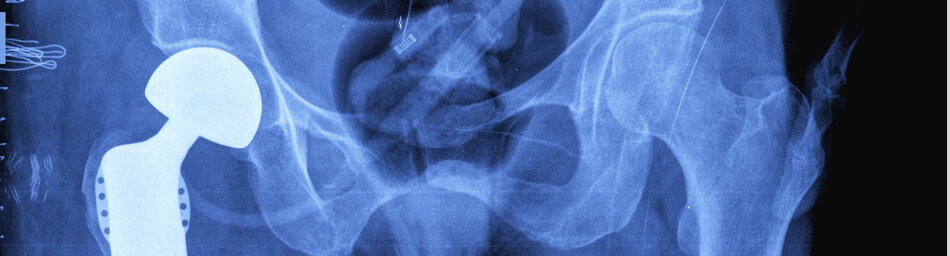

Hip Replacement Implants

Nearly 40 years ago, surgeons performed the first FDA-approved total hip replacement surgery(28). The implant inserted at that time “had a smooth, polished stainless steel stem and a plastic socket. Both pieces were cemented or glued into place.”(29)